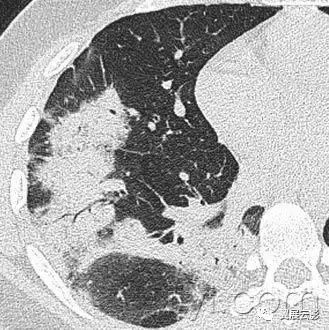

十八、小叶中心性:

小叶中心性异常包括(1)结节(2)树芽征,提示小气道病变(3)由于临近间质的增厚或者浸润导致小叶中心结果更加清晰(4)小叶中心性肺气肿导致的异常低密度。

附图为小叶中心性肺气肿